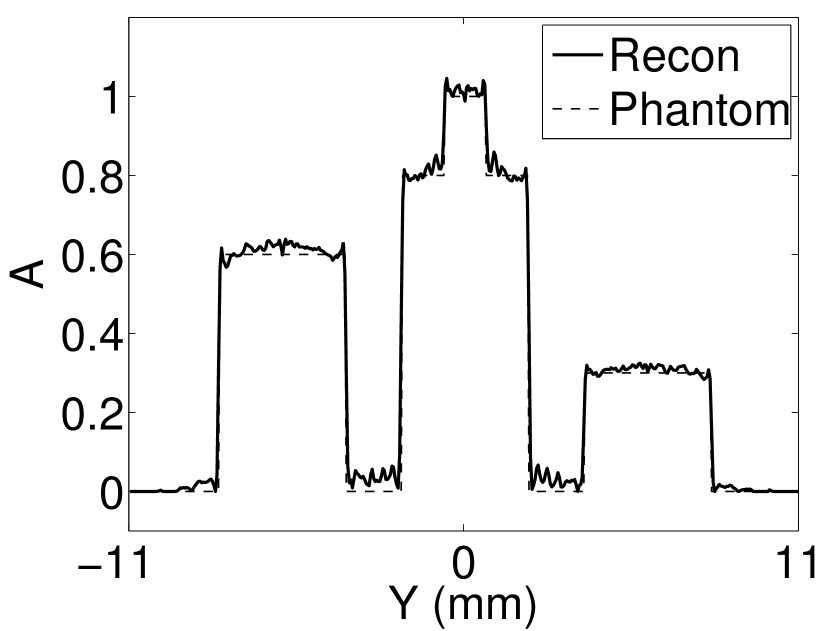

The images and EIRs reconstructed by use of the VP algorithm that was based on the 2D imaging model that neglected the SIR are shown in Figures 15 and 16. The latter figure contains results corresponding to different values for the regularization parameter . From Fig. 15, it can be observed that use of the conventional iterative method that utilized the measured EIR resulted in distortions and loss of details in the reconstructed images. Use of the VP algorithm improved the contrast and the details in the reconstructed images (Fig. 15(c) and 16(a)). Furthermore, the images reconstructed by use of the VP algorithm had a more uniform background.

In Figure 17, the results corresponding to use of the 3D imaging model that incorporated SIR effects are shown. The EIR estimated by the VP algorithm is also shown. In Figure 18, images and EIRs reconstructed by use of the VP algorithm with different regularization parameters values are shown.

Similar to the case described above where the transducer SIR was neglected, these results reveal that use of the VP algorithm can produce images with a cleaner background and enhanced spatial resolution than yielded by use of a conventional iterative algorithm that employed the measured EIR. For example, detailed information regarding the vessels near the organ’s periphery was better preserved by the VP algorithm than by the conventional iterative algorithm. These images corroborate our assertion that the VP algorithm can significantly reduce the artifacts and distortions in the reconstructed image. It is also worth pointing out that, unlike the numerical phantom studies, the artifacts and distortions in the images may be caused not only by the inaccurate EIR but also by other factors, such as neglecting acoustic heterogeneities and the variation of the EIRs among the elements of the transducer array. In such cases, the EIR estimated by the VP algorithm represents an effective system impulse response that minimizes the inconsistency between the measured data and the imaging model.